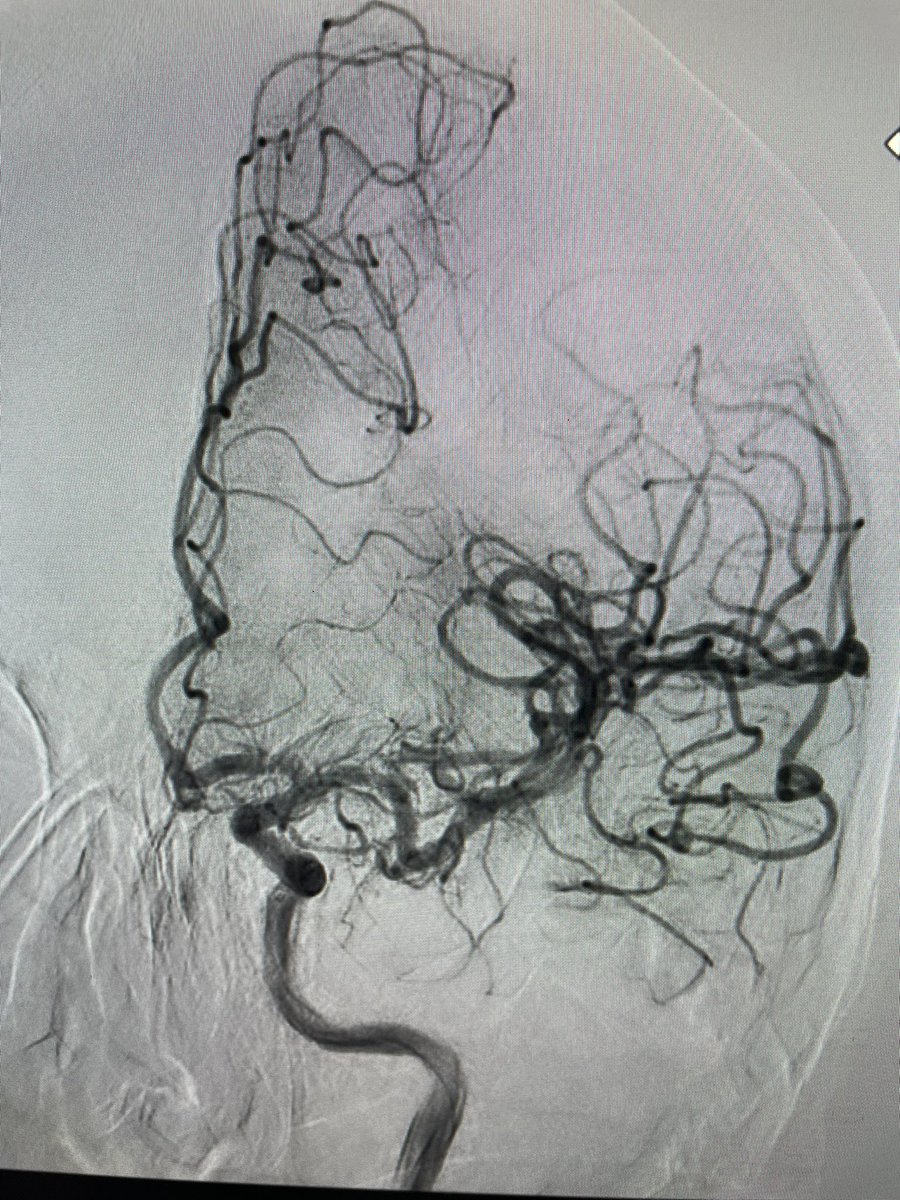

El Dr. Carlos Pérez@Justcharly9, nos resume en menos de 15 minutos los dos principales ensayos clínicos que comparan tratamiento Endovascular VS Quirúrgico (ISAT, IBRAT) de aneurismas rotos.